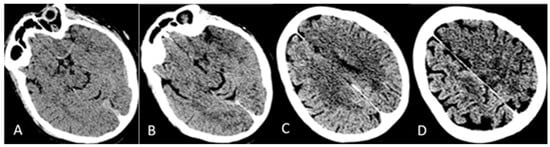

The patient was then admitted to the Neurology Unit. She appeared alert, with severe aphasia and right hemiplegia. She did not show signs of hemorrhagic diathesis, no petechiae, nor bleeding from the sampling sites. Therapy with 40 mg intra-venous (i.v.) dexamethasone; i.v. High Dose IgG (IgG-HD) 1 g/Kg once daily for two days; and subcutaneous (s.c.) fondaparinux 2.5 mg once daily was started. The patient’s clinical condition deteriorated rapidly. She went into a GCS 5 coma on the second day, with pupillary anisocoria from left > right, right hemiplegia, tachypnea, and severe respiratory failure (at EGA: pO2 64; pCO2 19; pH 7.5). A brain CT scan was then performed revealing a more significant enlargement of the ischemic cerebral lesion in the left hemisphere with transtentorial uncal herniation to the right of the third ventricle and the left lateral ventricle, obliteration of the suprachiasmatic cistern, and enlargement of the right temporal horn, as from incipient hydrocephalus, as is shown in Figure 4A–C.

Figure 4. CT Brain on last day. (A) Transtentorial uncal herniation compressing the midbrain bridge from left to right; blood secretion in the nucleocapsular and subnucleocapsular regions; (B) significant compression on the III and on the left SV, with significant shift to the right and hydrocephalus of the right SV with signs of transependymal CSF transudation; and (C) clear and diffuse cortico-subcortical hypodensity of ischemic-edematous significance in the anterior cerebral artery (ACA) and middle cerebral artery (MCA) vascularization territories, from “malignant” cerebral infarction; the artery territories partly preserved posterior cerebral (posterior occipitotemporal) results of left fronto-parietal decompressive craniotomy with brain herniation (“brain fungus”).